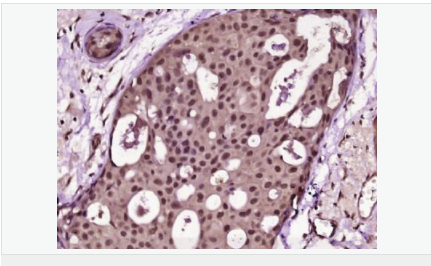

Ki67 antigen is the prototypic cell cycle related nuclear protein, expressed by proliferating cells in all phases of the active cell cycle (G1, S, G2 and M phase). It is absent in resting (G0) cells. Ki67 antibodies are useful in establishing the cell growing fraction in neoplasms (immunohistochemically quantified by determining the number of Ki67 positive cells among the total number of resting cells = Ki67 index). In neoplastic tissues the prognostic value is comparable to the tritiated thymidine labelling index. The correlation between low Ki67 index and histologically low grade tumours is strong. Ki67 is routinely used as a neuronal marker of cell cycling and proliferation.

細(xì)胞增殖標(biāo)志物(Proliferation Marker)

Ki67與PCNA一樣,為細(xì)胞增殖的一種標(biāo)記,在細(xì)胞凋亡中S、G2 、M期均有表達(dá),G0期缺如。

Ki-67增殖指數(shù)高低與許多腫瘤的分化程度、浸潤、轉(zhuǎn)移以及預(yù)后密切相關(guān),因此被廣泛作為各種惡性腫瘤的必檢項(xiàng)目之一。